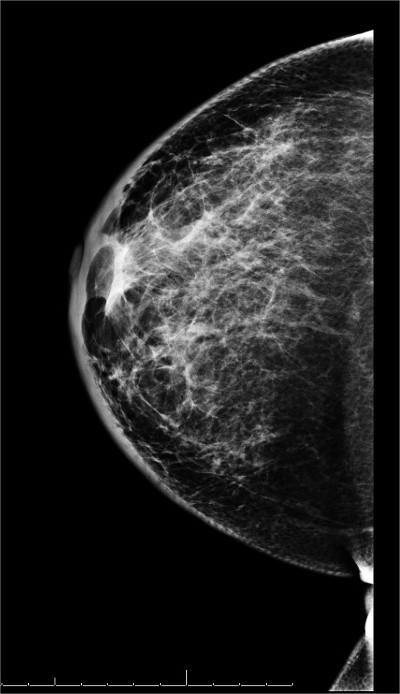

👉The mammogram shows trabecular thickening and an increased thickness of the skin.

👉Trabecular thickening is an increased prominence of linear structures in the breast, primarily corresponding to Cooper’s ligaments.

👉It is almost always seen in conjunction with skin thickening and indicates significant breast edema.

👉It has a number of different causes, including congestive heart failure, renal failure, venous or lymphatic obstruction, diffusely infiltrating carcinoma, and radiation.

👉When the cause is lymphatic obstruction, the obstruction can be the result of surgery, radiation, or lymphatic invasion by cancer.

👉Unilateral breast edema with increased trabecular and skin thickening sometimes occurs with congestive heart failure.

👉The pedal edema that develops during the daytime decreases at night and the fluid accumulates in the dependent breast in patients who sleep on their side.